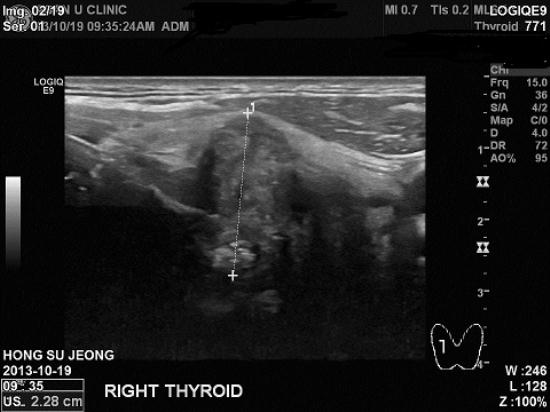

아산유외과 개원후 갑상선암 진단 8.

56세 남성분으로 건강검진상 이상소견 진단되어 본원에 세침검사 의뢰되어

시행한 갑상선 우엽 결절의 침생검상 유두암 진단되었습니다.

얼마전 아내분께서 같은 병으로 수술받은 후라 더욱 놀랍기만 할 뿐입니다.

'갑상선암은 여자만 걸리는거 아닙니까? 그래서 상상도 못 했네요.....'

라고 하시던 말씀이 자꾸 뇌리를 스칩니다.

드물긴 하지만 남성들에게도 갑상선암이 예외는 아닙니다.

빠른 쾌유를 기도합니다.